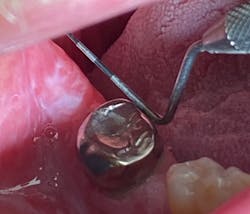

Clinically, the lesions were generalized, more prominent in the posterior buccal vestibular areas. White patches and collective striations were seen, measuring from 4 mm to 12 mm in size. They were painful to the touch and did not rub off with gauze. The patient said he noticed the start of the lesions on the tip of his tongue and on his lower lip, which appeared to be cracked and dry. See accompanying images.